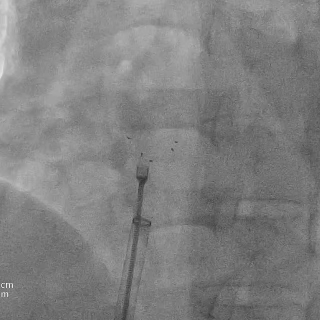

DSA下将前4个Mark点推出鞘管后,轻拉成型线使左盘面成型

再将输送系统整体后撤贴靠房间隔,超声下可见左盘贴合在房间隔上

逆时针旋转钢缆释放封堵器,5个Mark点聚拢